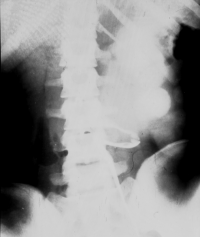

• Abbildung 17: Ureterabgangsstenose mit ausgedehnter Hydronephrose links

3. Retrograde Darstellung des hydronephrotischen linksseitigen Nierenbeckens